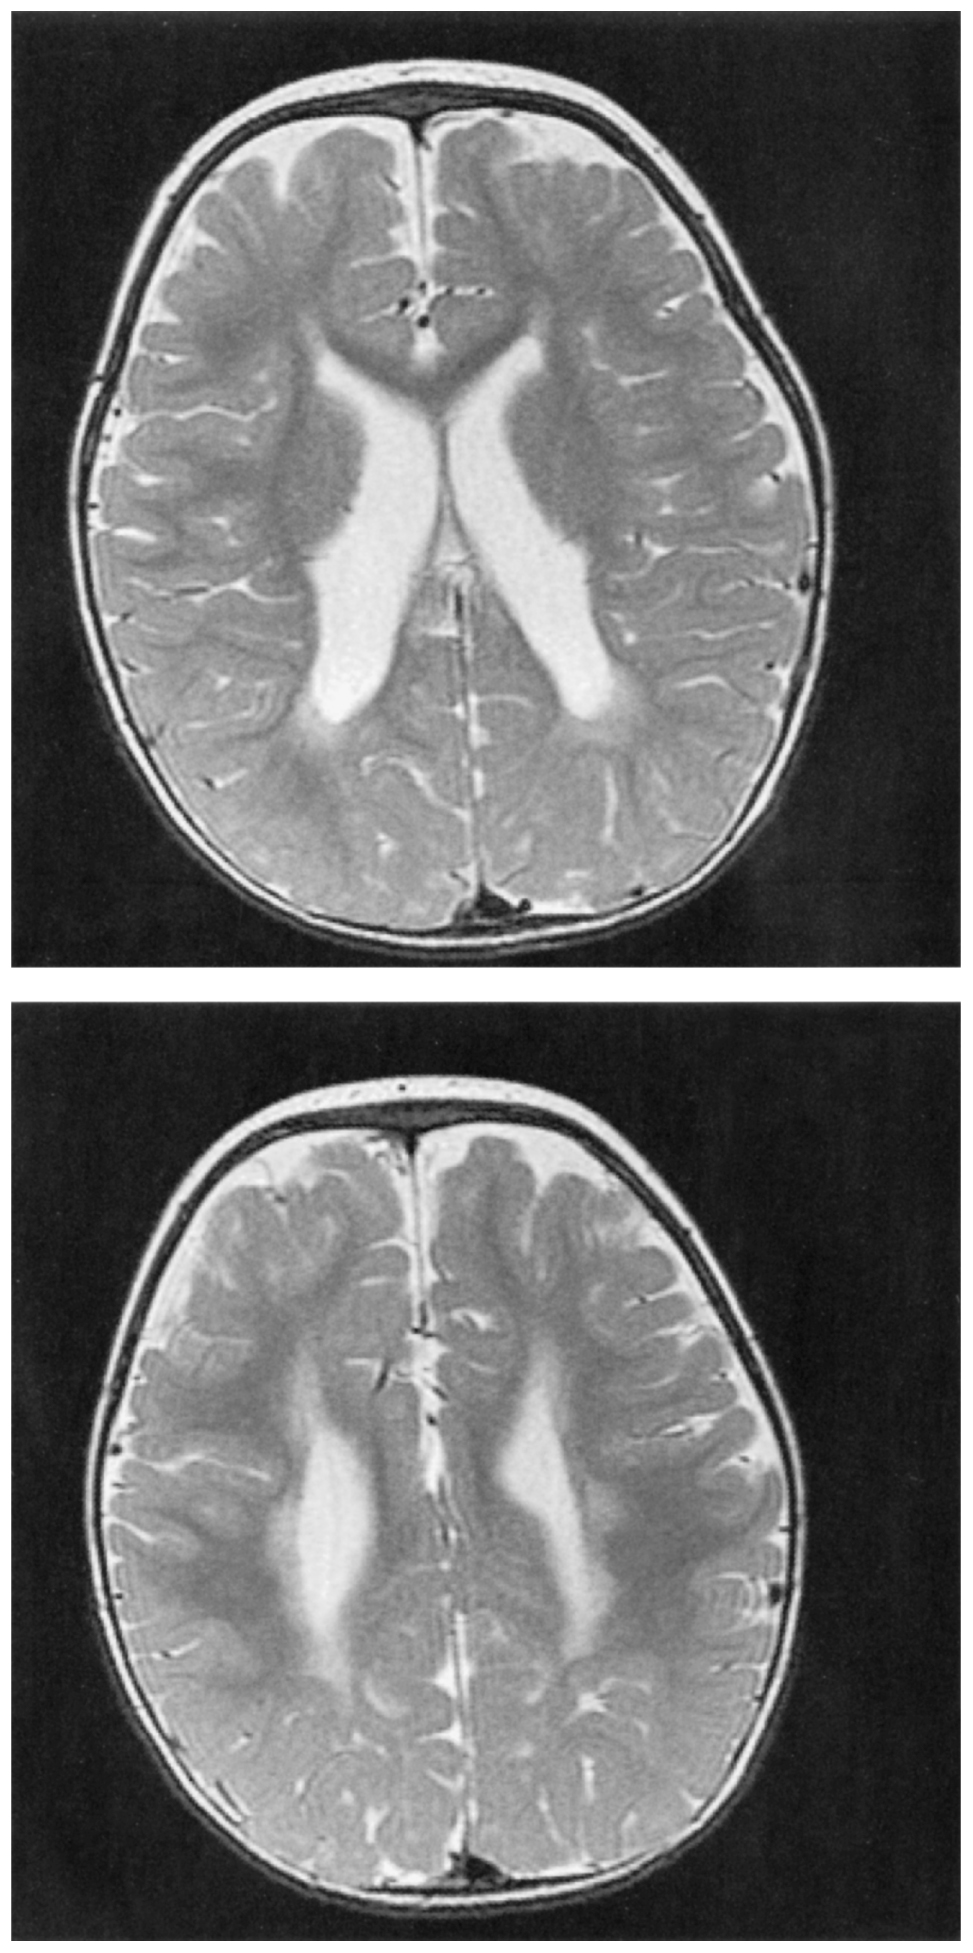

2歳の女児。早産児の定期外来のため母親に連れられて来院した。出生歴は,在胎29週,体重1,020g,Apgarスコアは7点(1分),8点(5分)で出生した。NICUに約4か月間入院した。入院中に光線療法を2日間行った。退院後は外来で定期的に経過観察されており,独歩がまだできない。意識は清明。身長82cm,体重10.5kg。体温37.1℃。脈拍112/分,整。呼吸数26/分。SpO2 98%(room air)。頭囲の拡大は認めない。心音と呼吸音とに異常を認めない。腹部は平坦,軟で,肝・脾を触知しない。皮膚に異常を認めない。下肢に筋緊張と腱反射の亢進を認め,尖足位である。Babinski徴候は陽性である。頭部単純MRIのT2強調像を下に示す。